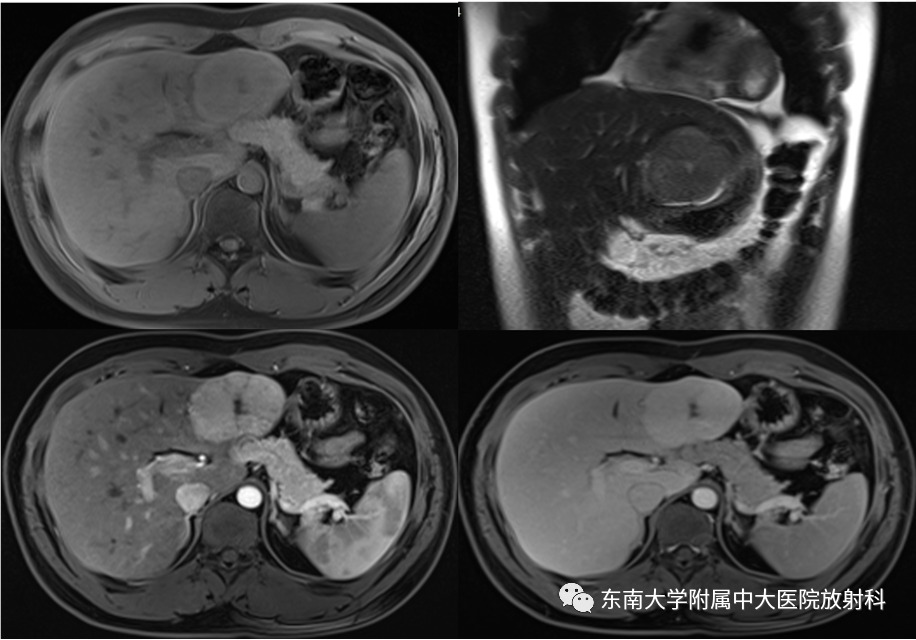

肝脏局灶性结节增生影像诊断

MRI增强